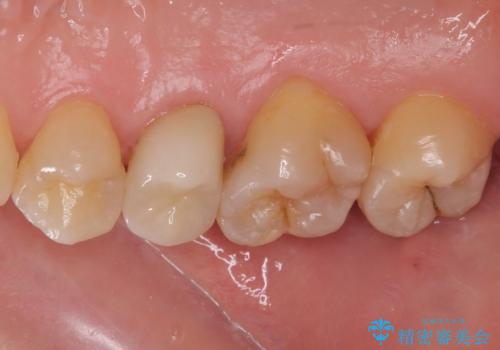

根管治療を行った奥歯は、再発防止や残された歯質を守るため、クラウンによる補綴治療が必要となります。

補綴後6ヶ月経過しレントゲンを撮影したところ、根尖周辺の病変が消失していることが確認できました。